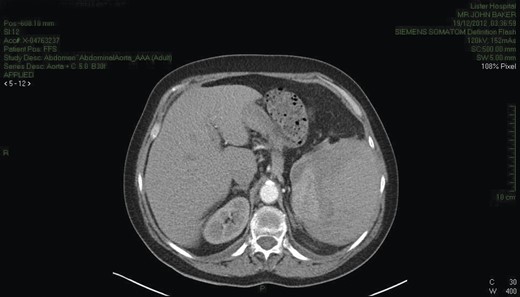

CT scan (Fig. 1) was consistent with splenic rupture. Laparotomy was performed and a large splenic haematoma with ∼1 l of blood in the abdomen and a splenectomy was performed. The postoperative period was complicated by a lower respiratory tract infection and some difficulty with mobilization but the patient made good recovery otherwise. During the post-operative period she developed a hypoglossal nerve palsy, which was assessed by the neurologist. An MRI scan failed to reveal a cause and the palsy settled spontaneously. She was discharged after 21 days.

CT chest/abdomen demonstrating a large splenic haematoma with hyper- and hypo-dense areas. High attenuation fluid is present within the pelvis consistent with blood.